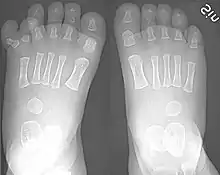

There are normally five toes present on each human foot. Each toe consists of three phalanx bones, the proximal, middle, and distal, with the exception of the big toe (Latin: hallux). For a minority of people, the little toe also is missing a middle bone. The hallux only contains two phalanx bones, the proximal and distal. The joints between each phalanx are the interphalangeal joints. The proximal phalanx bone of each toe articulates with the metatarsal bone of the foot at the metatarsophalangeal joint. Each toe is surrounded by skin, and present on all five toes is a toenail.